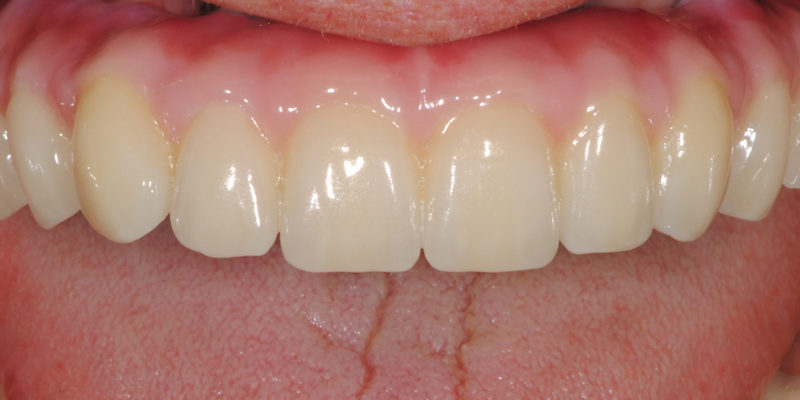

Ripristino dell'arcata superiore atrofica su impianti con ricostruzione estetica in zirconia e ceramica Category: Lavori ImpiantiMaggio 9, 2018Condividi questo ProgettoShare with FacebookShare with TwitterShare with Google+Share with PinterestShare with LinkedInProject navigationPreviousPrevious project:Ripristino dell’arcata superiore atroficaNextNext project:Ripristino dell’arcata superiore ed inferiore